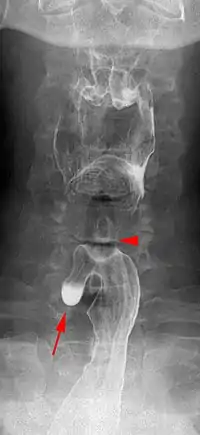

| Killian–Jamieson diverticulum. Arrowhead points at the closed upper esophageal sphincter, arrow points at the diverticulum partly filled with contrast medium. | |

The physicians that first discovered the diverticulum were Gustav Killian and James Jamieson. Diverticula are seldom larger than 1.5 cm, and are less frequent than the similar Zenker's diverticula. As opposed to a Zenker's, which is typically a posterior and inferior outpouching from the esophagus, a Killian–Jamieson diverticulum is typically an anterolateral outpouching at the level of the C5-C6 vertebral bodies, due to a congenital weakness in the cervical esophagus just below the cricopharyngeal muscle. It is usually smaller in size than a Zenker's diverticulum, and typically asymptomatic.[2] Although congenital, it is more commonly seen in elderly patients.[3]